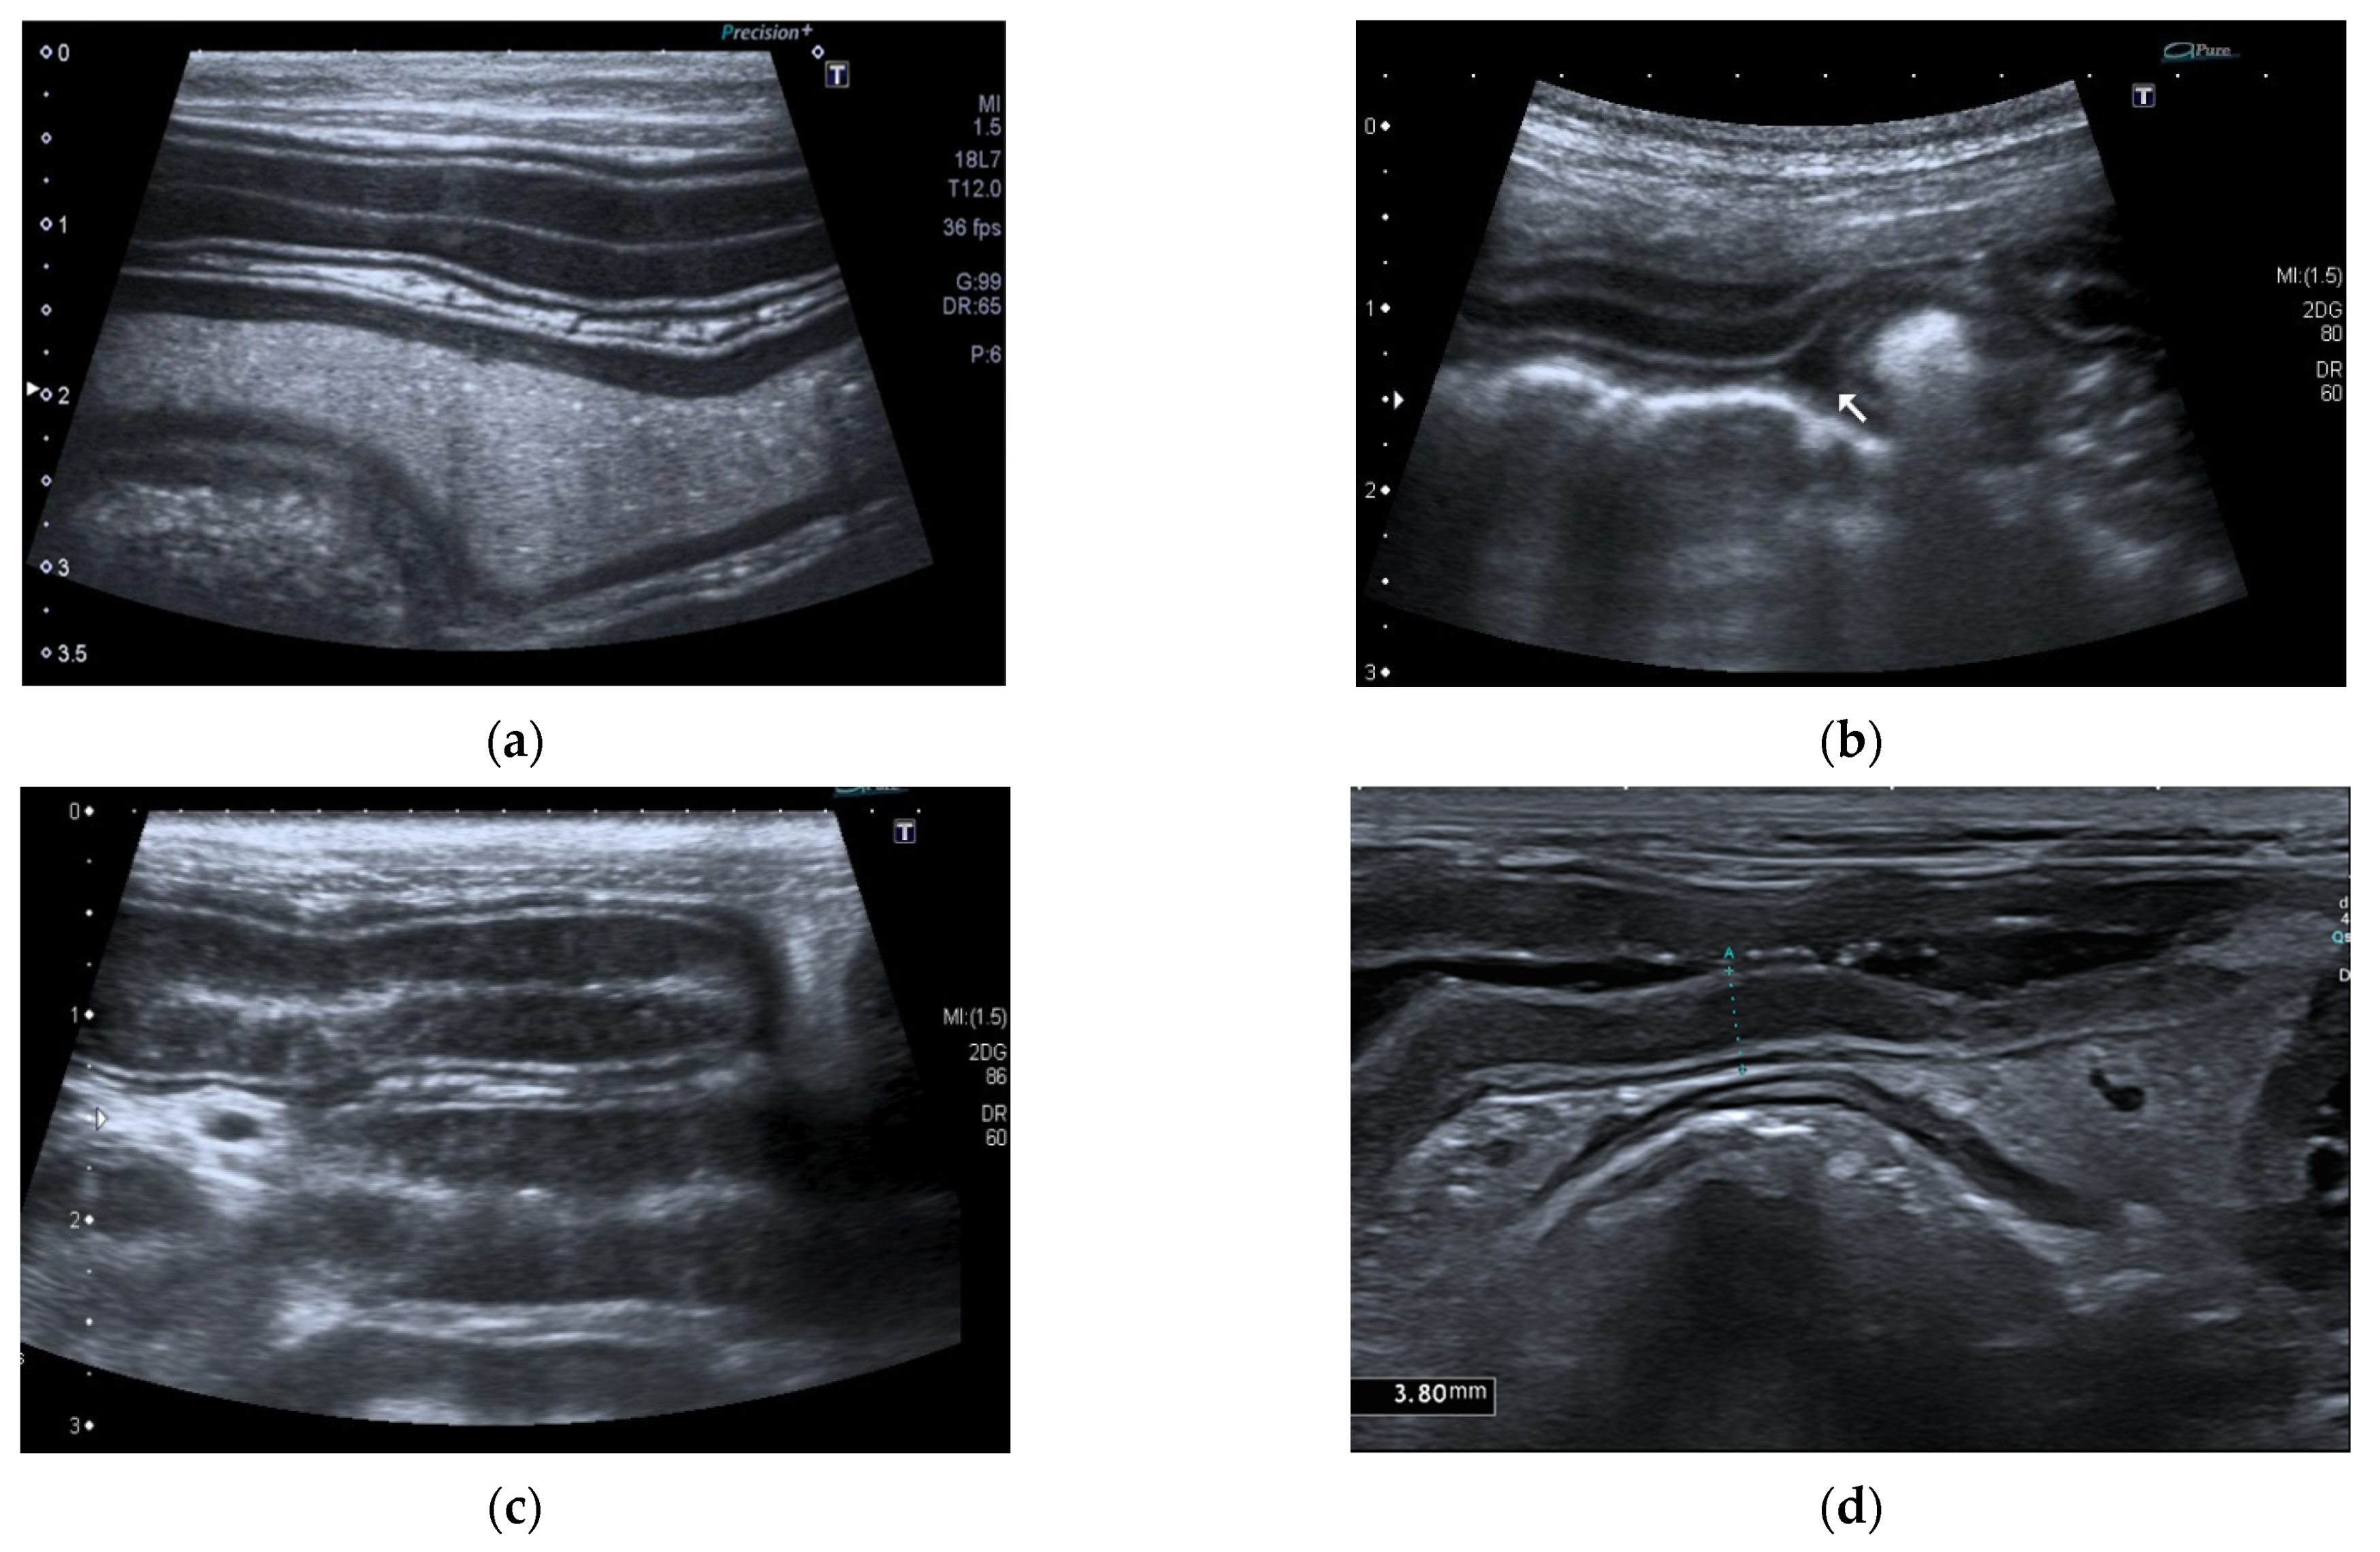

Pancreatic size was determined using calipers on a video frame or a still image. As described in the previous study, given that the pancreas has a triangular shape, it was considered a good compromise to measure its thickness perpendicular to the long axis [17]. Due to the low identification rate of the left pancreas in dogs, the pancreatic thickness was evaluated by measuring the right lobe located ventromedial to the right kidney and medial to the descending duodenum (Figure 1) [17].

Figure 1.

Ultrasound images (a) and (b) of the right pancreatic limb (between white arrows) with caliper measurement.